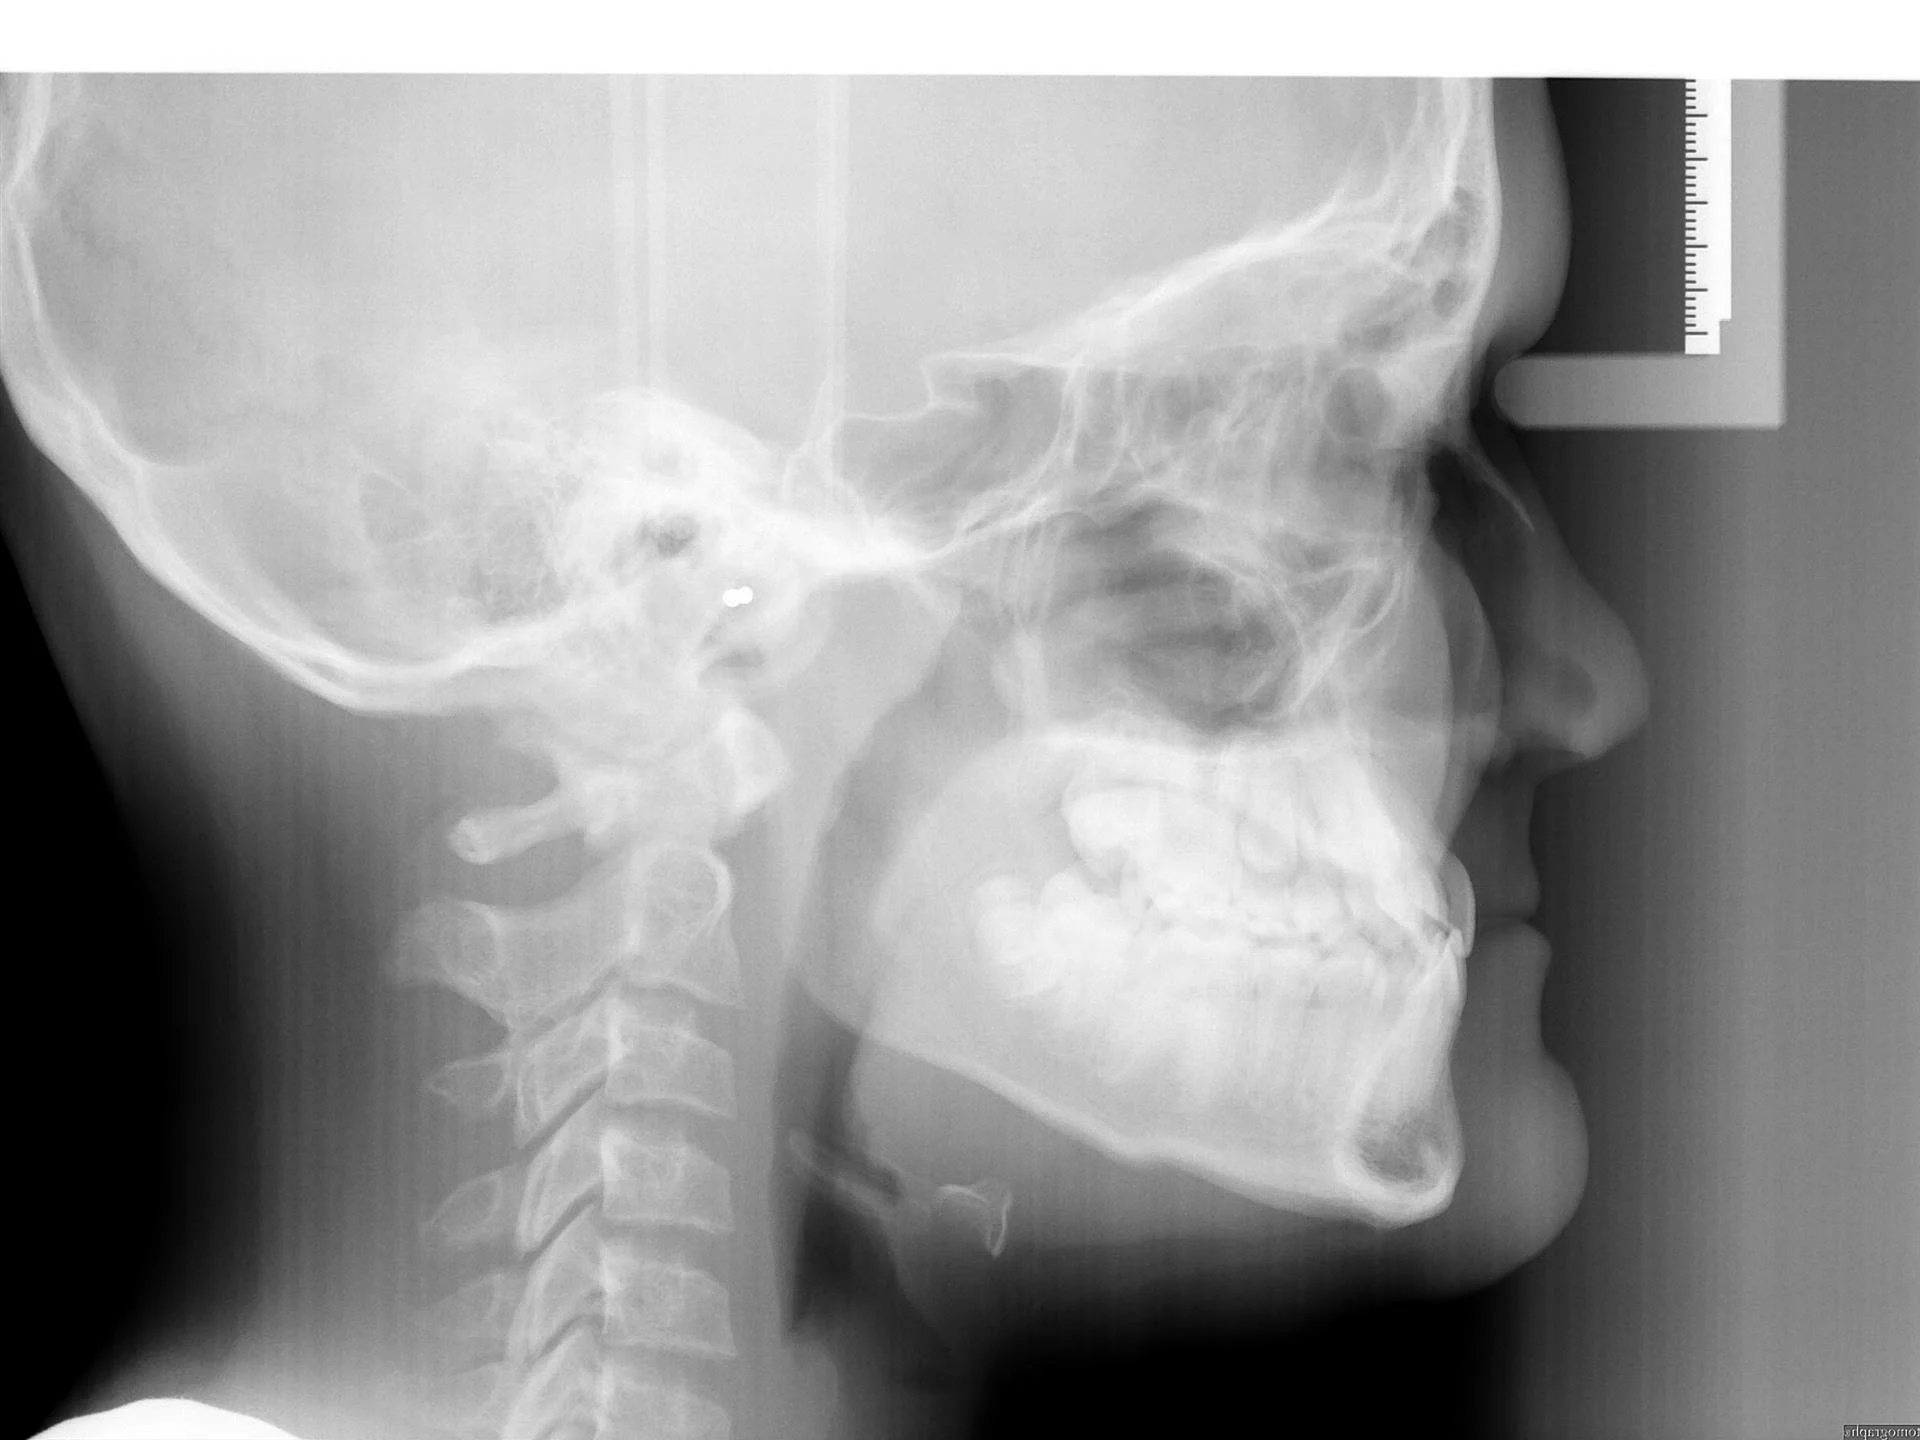

5.JPG